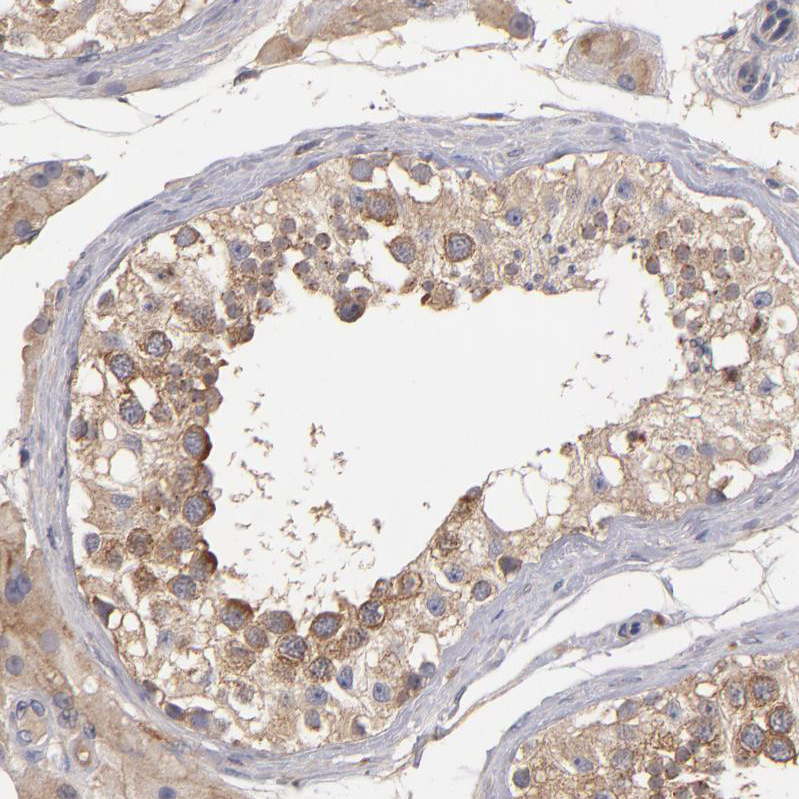

Immunohistochemistry analysis in human testis and liver tissues using HPA001882 antibody. Corresponding UPF3B RNA-seq data are presented for the same tissues.